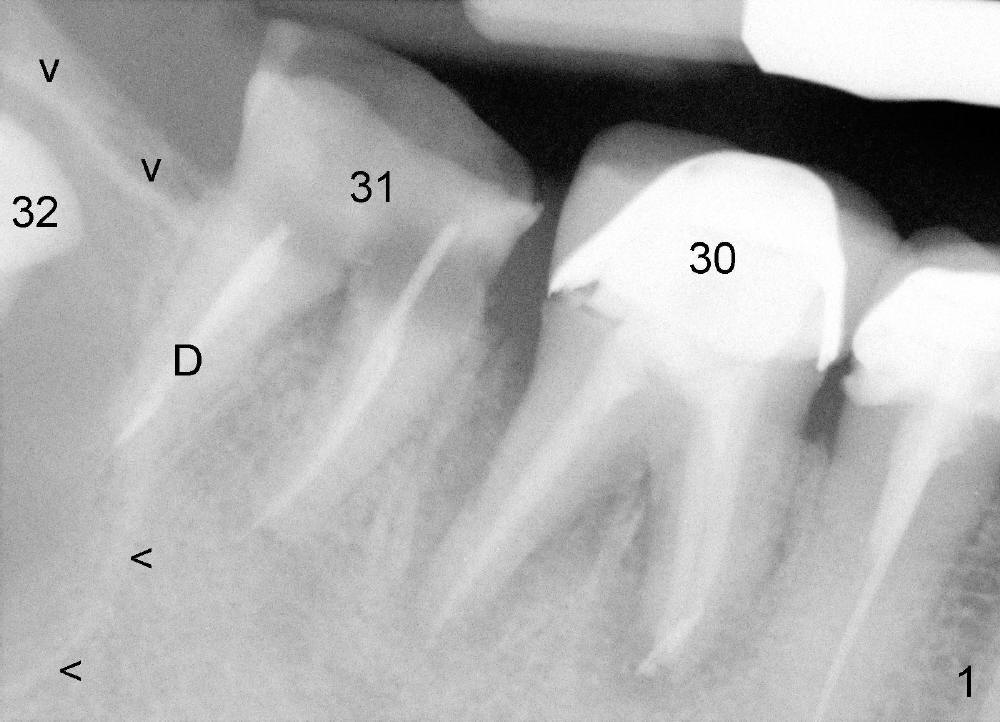

A 47-year-old man requests restoring the tooth #31 (Fig.1). It appears

that the best option is an implant. A close look reveals a possible cyst

(arrowheads) associated with #32. On the day of surgery, a panoramic X-ray